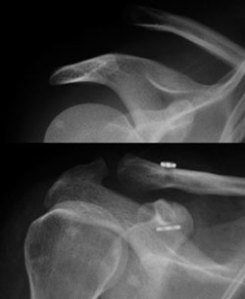

The x-rays will show a separation of the acromio-clavicular joint. This is sometimes termed “shoulder separation” as opposed to “shoulder dislocation”.

Doctors classify the dislocation based on the x-ray appearances and grade them accordingly.

The Type III to Type VI separations can be treated surgically. This is an example using the Arthrex tightrope technique for a Type V injury:

This is a patient of mine with painful type III separations and he wanted the joint to be reduced. Endobuttons were used as taught to me by my colleague Dr YW Lim: